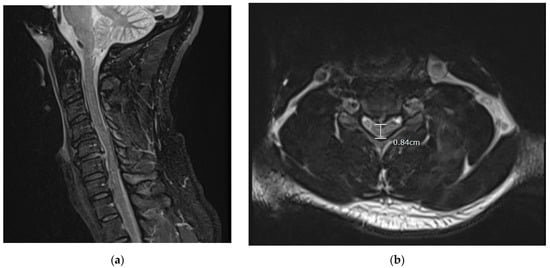

Physical examination found that the patient had 5/5 strength throughout except a 4+/5 distal right hand strength. The patient also had decreased sensation to light touch below the neck, which was worse on the right side. The patient did not have clonus or Hoffman’s sign, no Babinski’s sign, nor hyperreflexia. Initial MRI results showed a large 5–6 mm traumatic right paracentral posterior disc protrusion with disruption of the posterior disc annulus at the C5–C6 level with associated severe central spinal stenosis and ligamentous damage to the posterior longitudinal ligament (PLL). There was also mild to moderate central spinal stenosis secondary to smaller disc protrusions at the C3–C4 and C6–C7 levels (Figure 1). Initial MRI showed no osseous fractures of the vertebrae, nor asymmetry in the alignment of any faucet joints.

Figure 1. Preoperative MRI (STIR sequence sagittal (Figure 1a) and T2 axial (Figure 1b)) taken in the emergency department shows the pathology of C5–C6 posterior acute cervical disc herniation with increased signal in the posterior longitudinal ligament and severe spinal cord compression with cord signal change status post self-manipulation of neck. The encircled area also shows the protrusion of the posterior herniated disc causing spinal stenosis. MRI = magnetic resonance imaging.